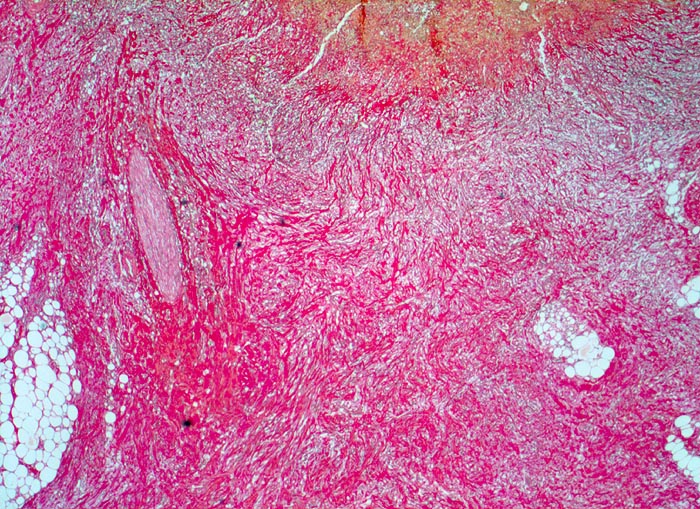

Das akute Ulkus ist rund, oval oder seltener polyzyklisch begrenzt und liegt meist im Schleimhautniveau. Das chronische Ulkus ist häufig kreisrund und im Längsschnitt trichter- oder treppenförmig. Die Schleimhautränder können lippenförmig über den Ulkusgrund hinausragen. Palpatorisch ist das chronische Ulkus aufgrund der narbigen Fibrose induriert. Die Schleimhautfalten laufen sternförmig auf das Ulkuszentrum zu. Das chronische Ulkus tritt zu 10%, das akute zu 25% multipel auf. Mikroskopisch zeigt das chronische Ulkus eine typische Schichtung (s. Bilder). Die Gefässe im Ulkusgrund zeigen eine starke Intimaproliferation mit teilweiser oder vollständiger Obliteration der Gefässlichtung. Morphologische Veränderungen in der übrigen Magenschleimhaut geben einen Hinweis auf die Ätiologie des Ulkus (Typ B oder C Gastritis).